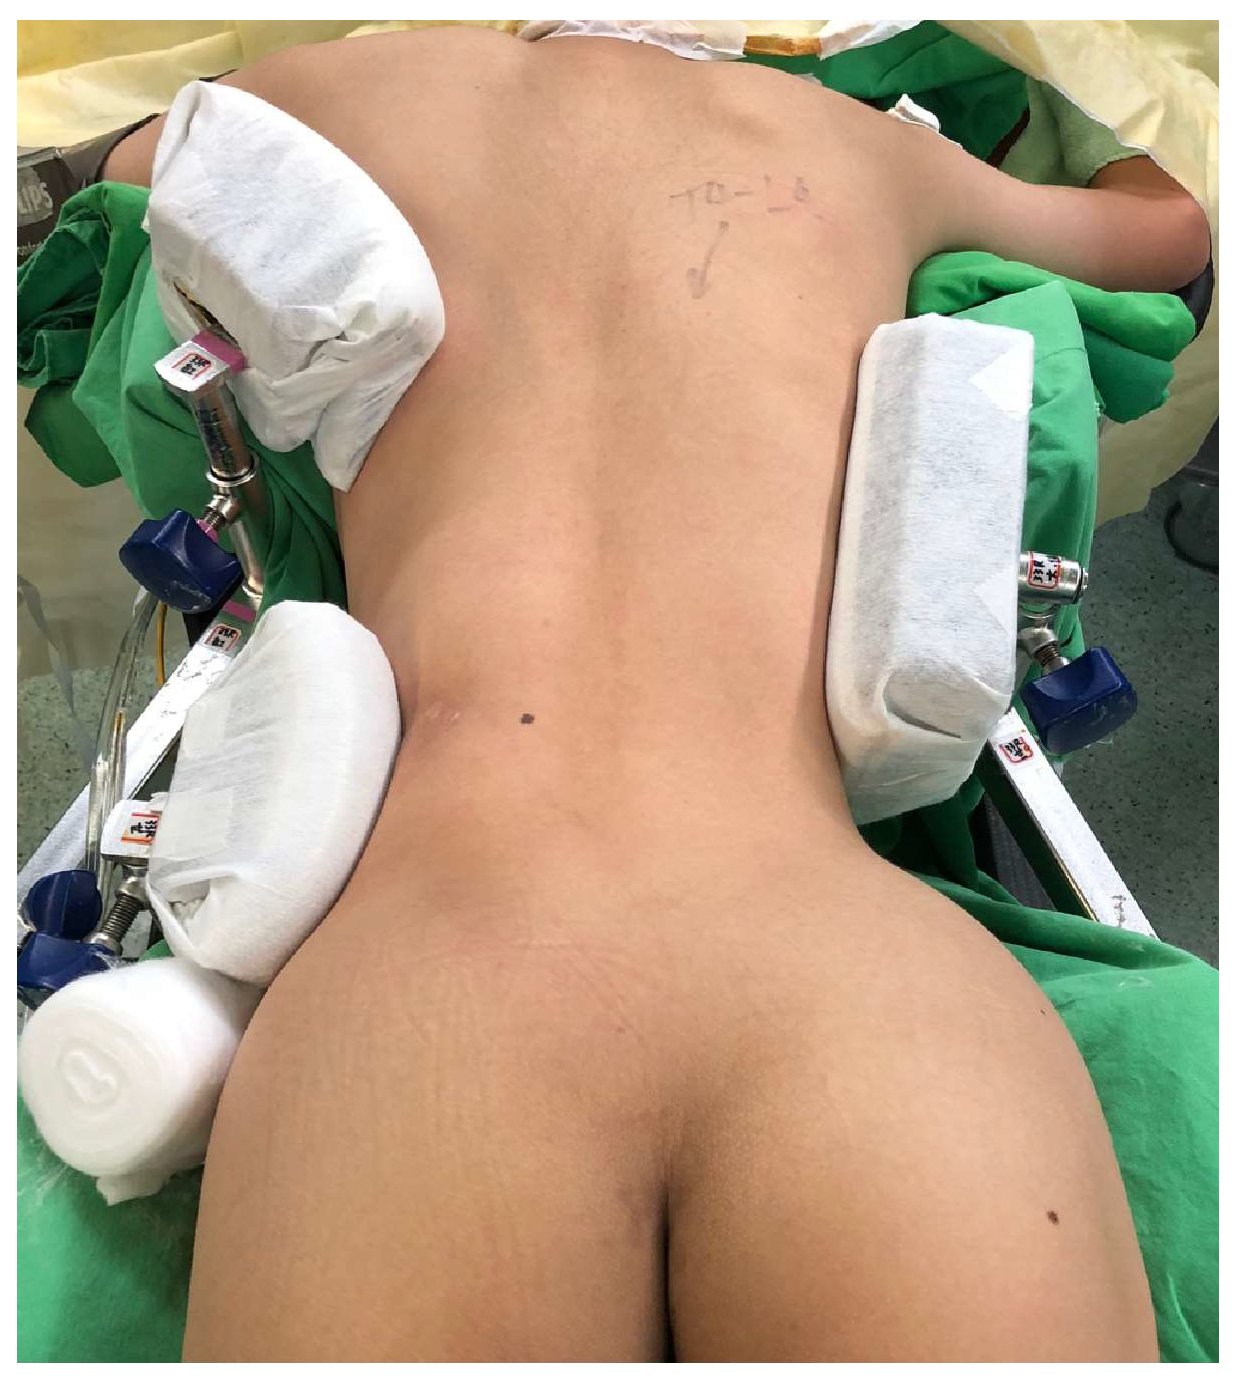

2.4. Surgical Procedure and Postoperative Care